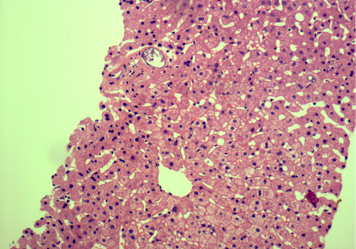

Microscopic (histologic) description

- Ova are mainly seen in the loose submucosa of large intestine, usually with formation of granulomas and infiltration by eosinophils and inflammatory cells

- Later the muscularis mucosa becomes involved and the overlying mucosa shows small superficial ulcers

- Fibrosis develops in chronic stage, when only calcified eggs are seen

Microscopic (histologic) images

Contributed by Nalini Bansal Gupta, M.D., Lisa Cerilli, M.D. and @zaalruwai83 on Twitter